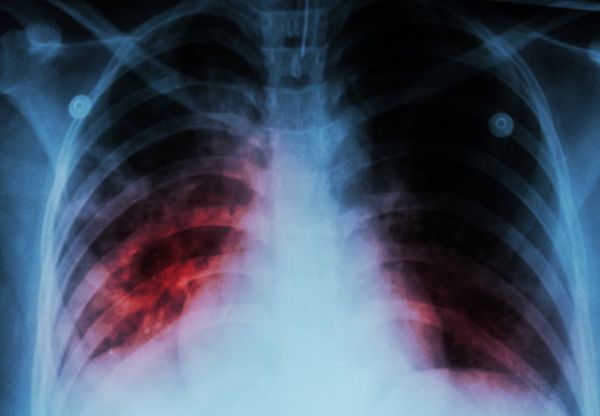

وی افزود: بیماری سل به وسیله یک باکتری ایجاد میشود؛ این باکتری به غیر از مو و ناخن که میتوان گفت بافت زنده نیستند، هر بافت زندهای در بدن را درگیر میکند و با توجه به محل و بافت درگیر شده علائم نیز طیف گستردهای خواهند داشت. از آنجایی که میکروب سل اکسیژن دوست است در ۸۰ تا ۸۵ درصد موارد ریهها را درگیر میکند در واقع شکل شایع بیماری سل، ریوی است. بنابراین شایعترین علائمی که برای بیماری وجود دارد، علائم تنفسی است؛ یعنی در سل ریوی شایعترین علامت سرفه طولانی مدت است. معنای این واژه به این صورت است که فرد حداقل دو هفته سرفه میکند. این سرفه هم میتواند با خلط همراه باشد و هم با خلط همراه نباشد.

رئیس اداره کنترل سل و جذام مرکز مدیریت بیماریهای واگیر وزارت بهداشت، ادامه داد: در شرایطی که مدت زیادی از آغاز بیماری گذشته باشد و بیماری پیشرفته شده باشد ممکن اسن سرفهها با خلط خونی همراه باشد. یکی از باورهای اشتباه در ذهن مردم این است که سرفههای مریض مسلول الزاما با بالا آوردن خون همراه است؛ اما این حالت تنها زمانی رخ میدهد که بیماری خیلی دیر تشخیص داده شود. بیشتر بیماران ما علامت سرفه با خلط خونی را در زمان تشخیص ندارند.

وی درباره سایر علائم ابتلا به سل، تصریح کرد: سرفه با شرایط ذکر شده که شاه علامت ابتلا به سل است میتواند همراه با تب، بیاشتهایی، کاهش وزن و حتی در موارد پیشرفته تنگی نفس از علائم ابتلا به سل باشد.